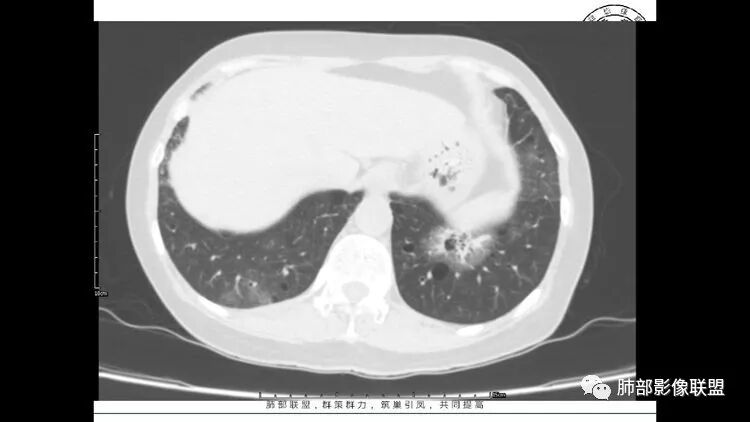

胸CT:1.双肺多发囊性变,以中下肺为主,病变边缘可见肺动脉,部分囊内可见分隔及肺动脉,双下部分肺野周围可见小叶中心结节及树丫征。

2 左肺上叶尖后段 右肺上叶前段 右肺下叶外基底段 结节影,边界清楚,可见柔软毛刺,左肺下叶后基底段混合密度影。

1.左下肺腺癌;2.两肺弥漫性病变(多发囊腔、部分囊壁不规则,分布无特异,结节,空洞,树芽征,GGO),结合眼部情况首先考虑LIP,不典型感染(病毒或其他)待排。

双肺多发磨玻璃结节病灶,内见实性成分及蜂窝,小泡征,考虑腺癌,淋巴瘤待排除,双肺多发肺气囊,沿支气管血管束分布,双肺多发小结节,部分小叶中心分布、部分位于胸膜下,边缘模糊,符合LIP,综合考虑LIP合并淋巴瘤或腺癌

左肺下叶混杂密度病灶,其内可见空泡,周围ggo清楚,考虑浸润性腺癌。双肺散在多发薄壁囊腔和实性结节,以胸膜下及血管旁分布位于,气囊可见血管贴边征,双肺小叶间隔及中央间质增厚,局部可见磨玻璃影及树芽征,纵隔内淋巴结肿大,考虑LIP

综上,考虑左下肺浸润性腺癌+LIP

双肺多发大小不等囊腔,可见薄壁,部分囊腔内可见血管影,伴双肺多发结节,结合患者眼病及类风湿病史,考虑LIP可能大。另左肺下叶磨玻璃结节,边界清晰,内可见空泡,伴纵膈多发肿大淋巴结,不除外浸润性腺癌可能。

常规分析:右眼红疼1天,滴眼史两年,有类风湿病史,考虑有干燥综合征(SS)可能,需要了解自免抗体检测情况,双肺囊变需要考虑LIP,另右上叶前段GGO要鉴别腺癌或转移可能,右下叶背段多发树芽改变,双肺多发实性小结节,结核?左下肺混合性GGO考虑侵润性腺癌可能,双侧胸膜下多发结节,部分合并GGO改变,右侧腋窝及纵隔淋巴结多见,转移?最后问题来了,这个病人一元(腺癌合并转移,包括整个囊变,实性结节,胸膜下都是转移)?二元(LIP合并腺癌伴转移或者淀粉样变基础上的LIP)?三元(LIP+结核+腺癌伴转移)?